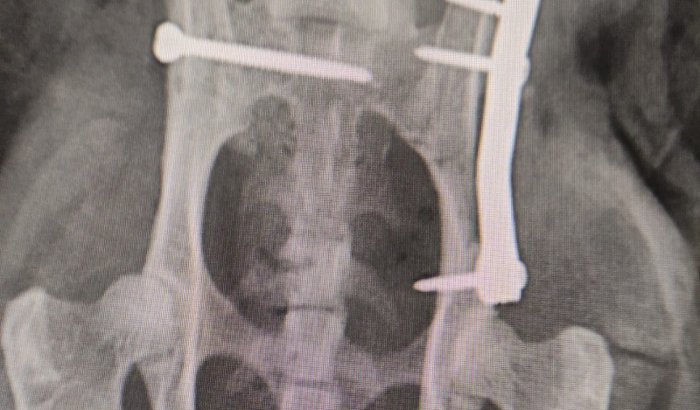

acabou sendo atropelAda e fraturou a Pelve: fratura completa em ílio direito, presença de pequenas esquírolas adjacentes, a maior delas mede aproximadamente 1,60 cm, luxação sacroiliaca esquerda! E precisara fazer uma cirurgia com ortopedista. Infelizmente ! ate agora já foi gasto com consulta, rx, ultrassom, sedação, diária até quarta à noite e exame de sangue totalizando 935,00

a cirurgia saíra 2000 mais 300 da anestesia ,fora As diárias até a alta

tbem terá as sessões de fisioterapia após a cirurgia.